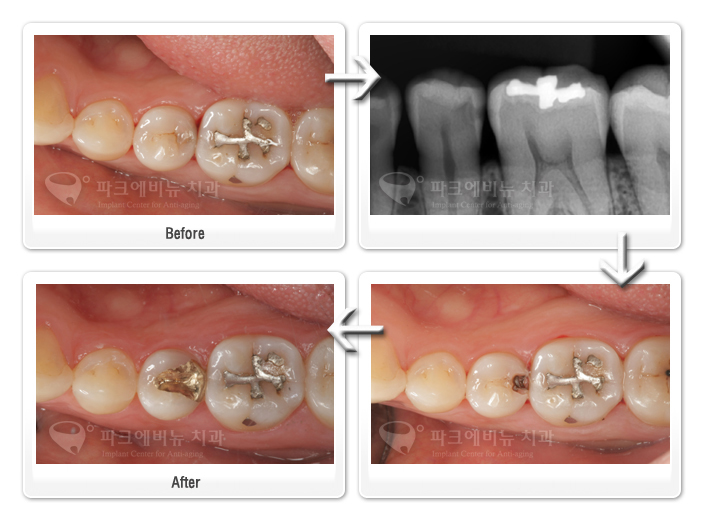

- 치아 사이 면이 썩었는데 왜 인레이를 해야하는 걸까? 또는 예전에 때워 놓았던 레진이나 아말감의 크기는 작은데, 교체 할 때는 왜 인레이 치료를 해야하는 걸까?

라는 의문을 가질 수 있다. 그 이유를 다음 환자를 예로 들어 설명하겠다.

치아 사이 충치는 초기 단계에서 육안으로 관찰하는 것 만으로는 건강한 치아와 구별 하기 힘들다. 따라서 진행이 어느정도 되고 나서야 육안으로 발견하는 경우가 많다. 위 환자는 내원 당시 두번째 작은 어금니가 치아가 검은 빛을 띄어 충치가 의심되었다. 그래서 엑스레이를 찍어 본 결과 큰 어금니와의 사이에 충치가 생겼음을 확인 할 수 있었다. 치아 사이 충치는 씹는 면이 썩지 않았다고 할지라도 치아 사이가 벌어져 있지 않은 이상 치료가 힘들기 때문에 씹는 면에서 접근 해야 한다. 따라서 치료의 범위가 치아 사이 면 뿐 아니라 씹는면 까지 확장되기 때문에 어금니가 받는 저작력을 감당하기 힘든 레진충전 치료를 하는 것은 부적합 하다.

두번째 사진의 환자는 위쪽 어금니를 아말감으로 떼워 놓았었다. 오랜 시간이 지나면서 아말감은 조금씩 깨지면서 떨어져 나가고 2차 충치 또한 생기게 되었다. 2차 충치를 제거하면서 삭제되어지는 치아의 양은 자연스럽게 늘어난다. 이 때문에 레진과 같이 단순하게 떼워 넣는 치료로는 치아를 튼튼하게 보강하기 힘들다. 치료 전과 후 사진을 비교해 보아도 삭제된 치아의 양이 확연히 늘어났음을 알 수 있다.